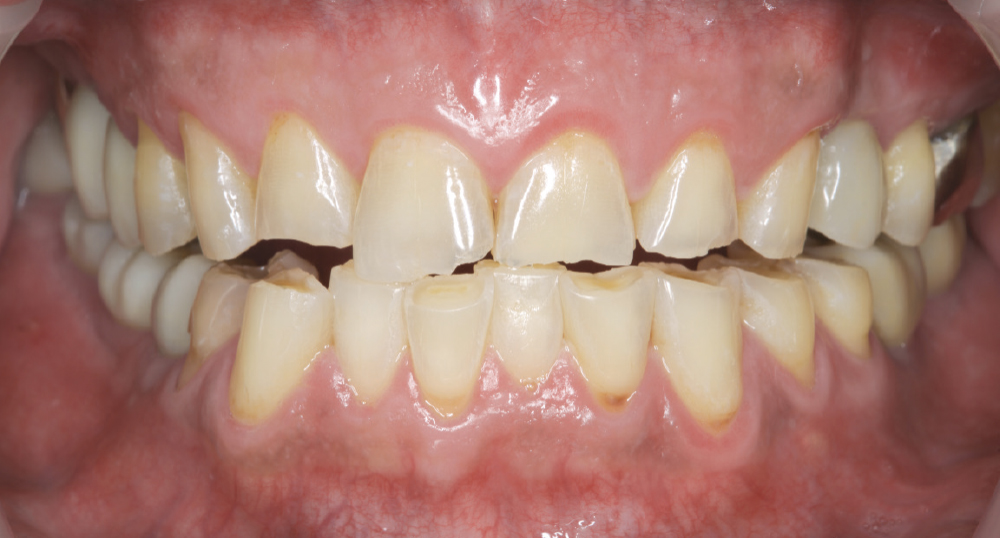

Implant post in socket

Finished Implant Restoration